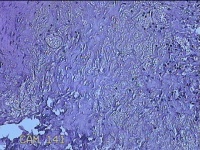

性别

女

年龄

28岁

临床诊断

1.疖肿病 2.皮脂腺囊肿

一般病史

外阴部起丘疹疼痛一周。

标本名称

外阴部包块

大体所见

灰白暗红色包块1x0.7x0.3cm一个,表面糜烂。